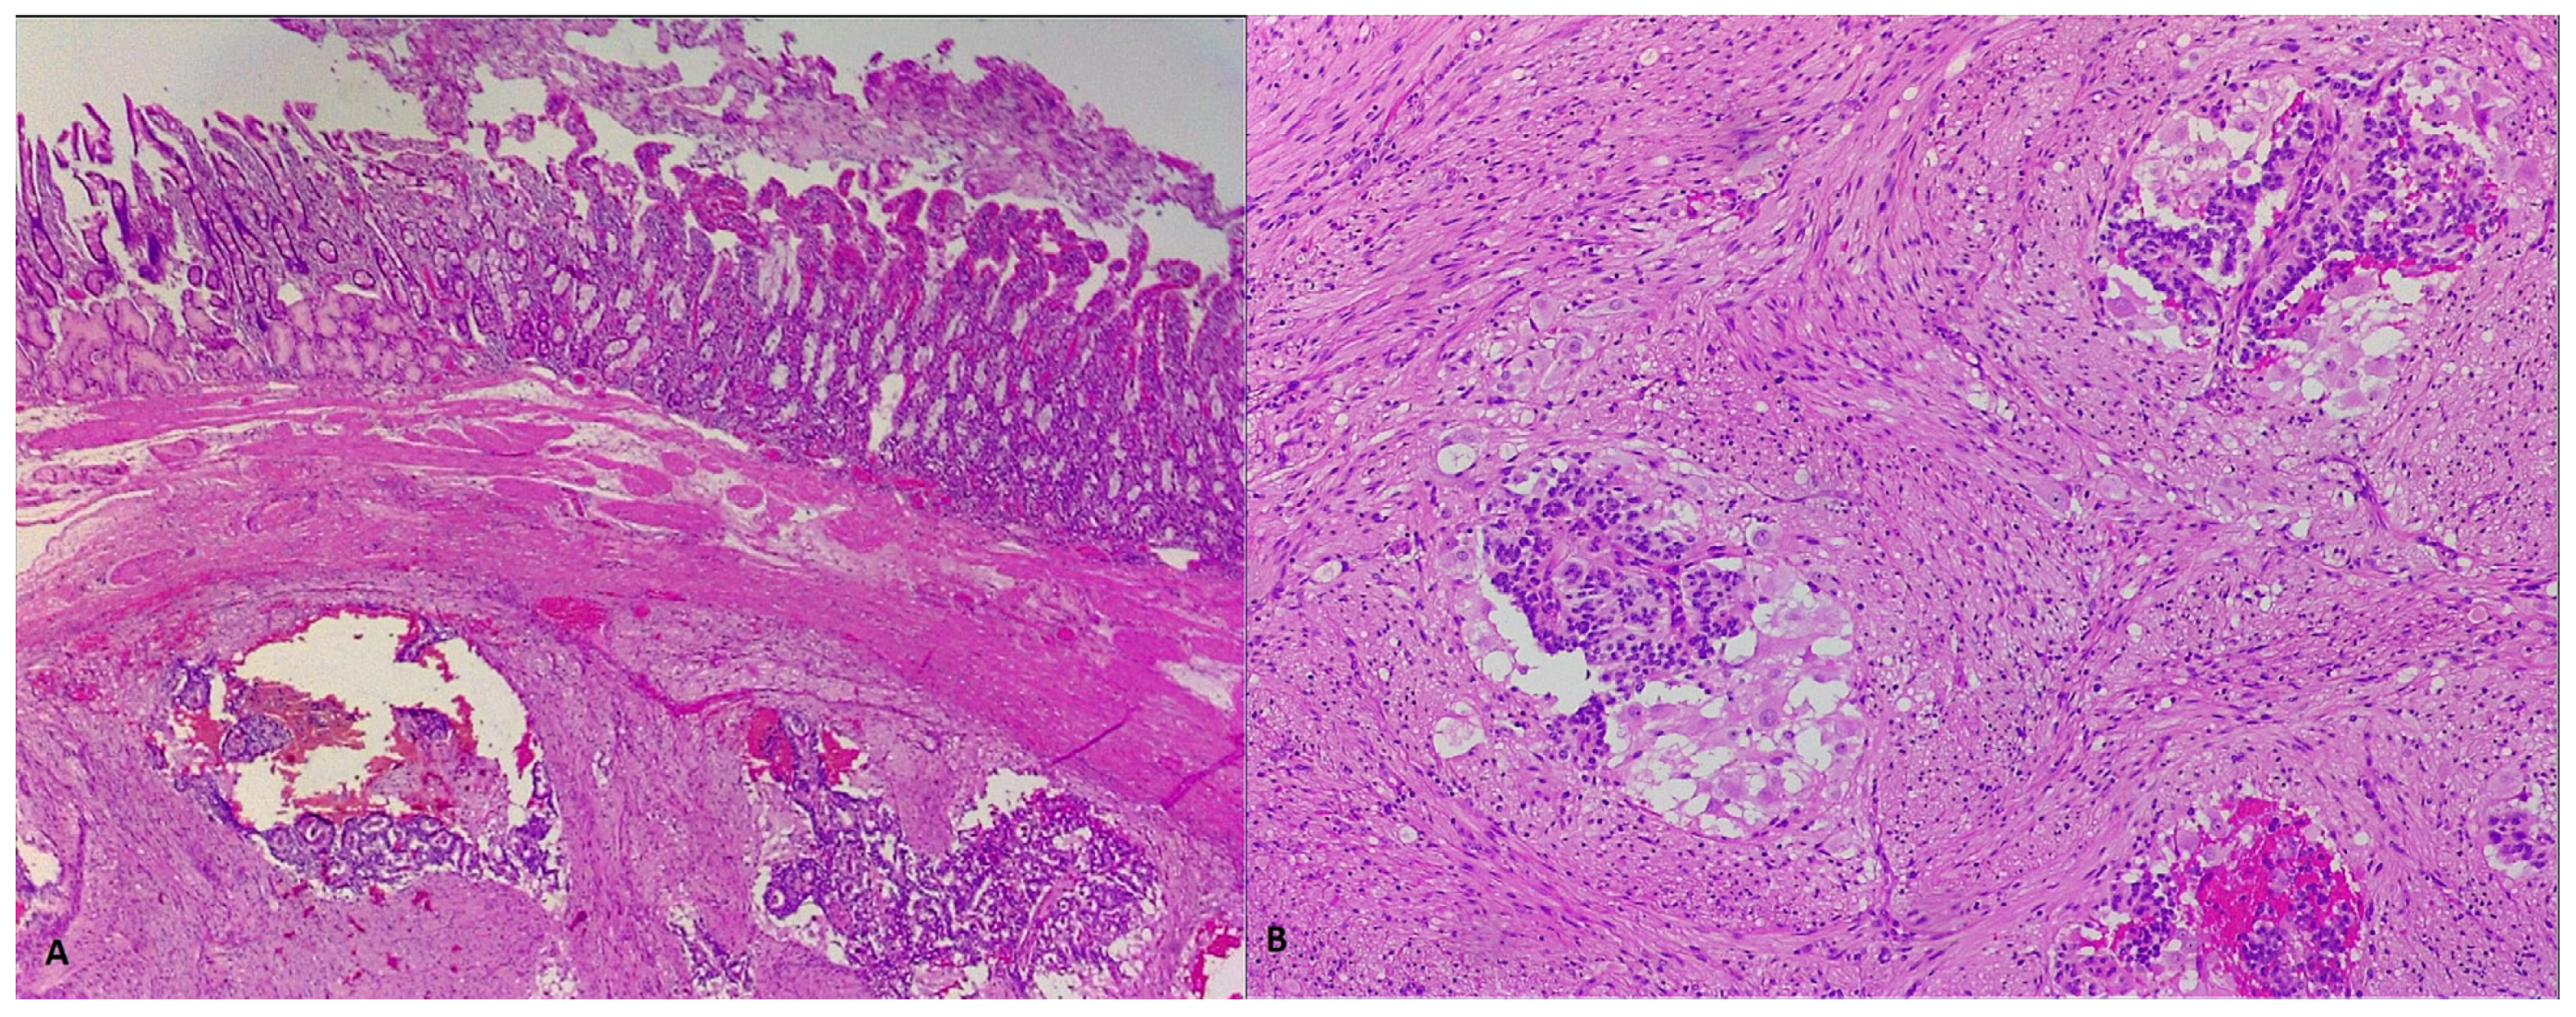

2. Case Report 1

3. Case Report 2